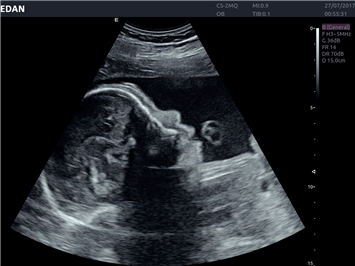

EDAN Acclarix LX4 представляет собой инновационную ультразвуковую систему, построенную на усовершенствованной платформе Acclarix. Сочетание высокого качества визуализации с интеллектуальным рабочим процессом делает эту систему оптимальным выбором для клиник, ценящих эффективность и экономичность.

• 3D/4D-визуализация с автоматическим редактированием объема (eFace)

• Автоматизированные измерения в акушерстве

• Акушерства и гинекологии